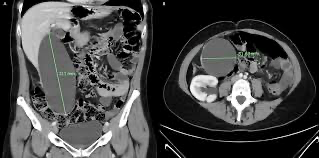

급성 담낭 수종 (acute hydrops)

• 정의: 결석, 세균감염, 담도의 선천 기형 없이 일어나는 급성 비염증 담낭의 확장

• 진단: 복부 초음파, CT

** 정상 GB는 길이 7-10cm, 직경 3-4cm이며 이를 초과하는 수치에서 진단한다.